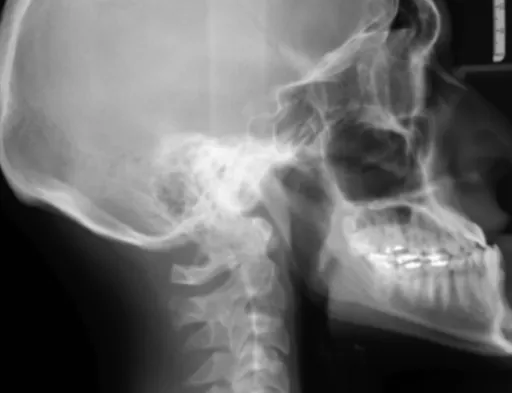

CT 혈관 조영술 (Computed Tomography Angiography, CTA)

X선을 이용해서 혈관을 촬영하는 검사예요. 조영제를 혈관에 주입해서 혈관을 더욱 선명하게 볼 수 있도록 해준답니다. 마치 야간 투시경으로 보는 것처럼 혈관이 또렷하게 보여요.